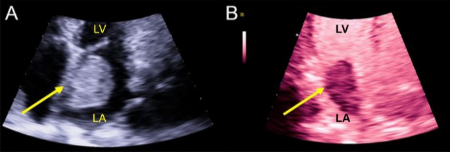

• اکوکاردیوگرام: اکوکاردیوگرام ترانستوراسیک معمولاً میتواند میگزوم را نشان دهد. اما ممکن است به اکوکاردیوگرام ترانسمریایی نیاز باشد تا تومورهای کوچک را بررسی کرده یا مکان اتصال تومور به قلب شما را مشاهده کند.

در طول معاینه فیزیکی، پزشک شما با استتسکوپ به صدای قلب شما گوش میدهد. میگزوم ممکن است باعث ایجاد یک صدای غیرعادی در قلب به نام «صدای تومور» شود. این صدای میگزوم است که به طور موقت دریچه میترال را مسدود میکند.